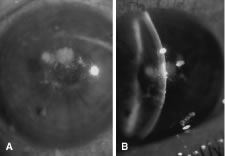

In the early stages of infection, filamentous fungi produce signs that are readily distinguishable from yeast or bacterial keratitis. The most distinctive sign is the presence of delicate, fine, feathery, opalescent, gray-white or yellow-white material in the anterior stroma, surrounded by scant cellular infiltrate or edema (Fig. 1). The epithelium may be intact. The overlying epithelium may be granular and the surface elevated and irregular in contour. Linear infiltrates typically extend into the adjacent stroma. Multiple discrete opacities may develop outside the perimeter of the principal focus of inflammation, either separated by clear stroma or linked by fine linear collections of inflammatory cells and material (Figs. 2 and 3). In the absence of inflammation in the adjacent stroma, branching hyphal fragments may be visualized by biomicroscopy (Figs. 4 and 5). Confocal microscopy may also detect hyphal elements within the stroma.28,29 Peripheral infection resembles noninfectious marginal infiltrative and ulcerative keratitis (Fig. 6). Multifocal keratitis may develop after contact lens wear or injury by multiple projectiles (Fig. 7). In the early stages, iritis is present and the intraocular pressure remains normal. Inappropriate, empirical therapy of fungal keratitis with topical fluoroquinolone or aminoglycoside antibiotics may suppress or eliminate the superficial elements but allow extension of the organisms into the stroma because these agents may possess selective antifungal activity.4,30,31

There is no distinguishing clinical sign by which to recognize the genus or species of the infectious filamentous fungus. F. solani is the most virulent organism and typically produces rapidly progressive infection characterized by epithelial and stromal ulceration, dense stromal necrosis, abundant cellular infiltrate, and edema in the adjacent stroma and hypopyon (Figs. 8 and 9). Delicate feathery components are transient. Individual hyphal fragments are rarely visualized. Infection by certain species of Aspergillus and Scedosporium (Figs. 10 and 11) resembles F. solani keratitis and progresses rapidly. Infection by less virulent organisms, such as Curvularia and Alternaria species, produces small, focal (less than 3-mm diameter) areas of nonnecrotizing stromal inflammation with delicate feathery borders (see Fig. 1 and Fig. 12). Macroscopic pigmentation may develop in keratitis caused by Alternaria, Curvularia, and other dematiaceous fungi (Fig. 13).4,11,14 The central component may progress to dense, opaque, gray-white suppuration in the deep stroma without enlargement in total area and may be accompanied by mild inflammation in the adjacent stroma. Iritis is minimal to moderate. Infection caused by other, relatively less virulent organisms resembles herpes simplex or noninfectious keratitis (Fig. 14).